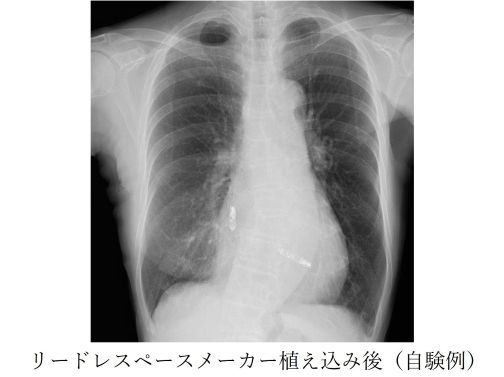

② リードレスペースメーカー

リードレスペースメーカーはリードがなく電池本体のみで心拍数を感知しペーシングを行います。足の付け根(大腿静脈)からカテーテルを用いて植込みます。局所麻酔(もしくは全身麻酔)で行い、所要時間は1時間ほどです。早期から離床でき退院後も身体制限がほとんどありません。体外からはペースメーカーは全く分からず、リード断線や感染症の危険性が少なく、ご高齢の方、透析の方、ペーシング頻度が少ない方に行います。